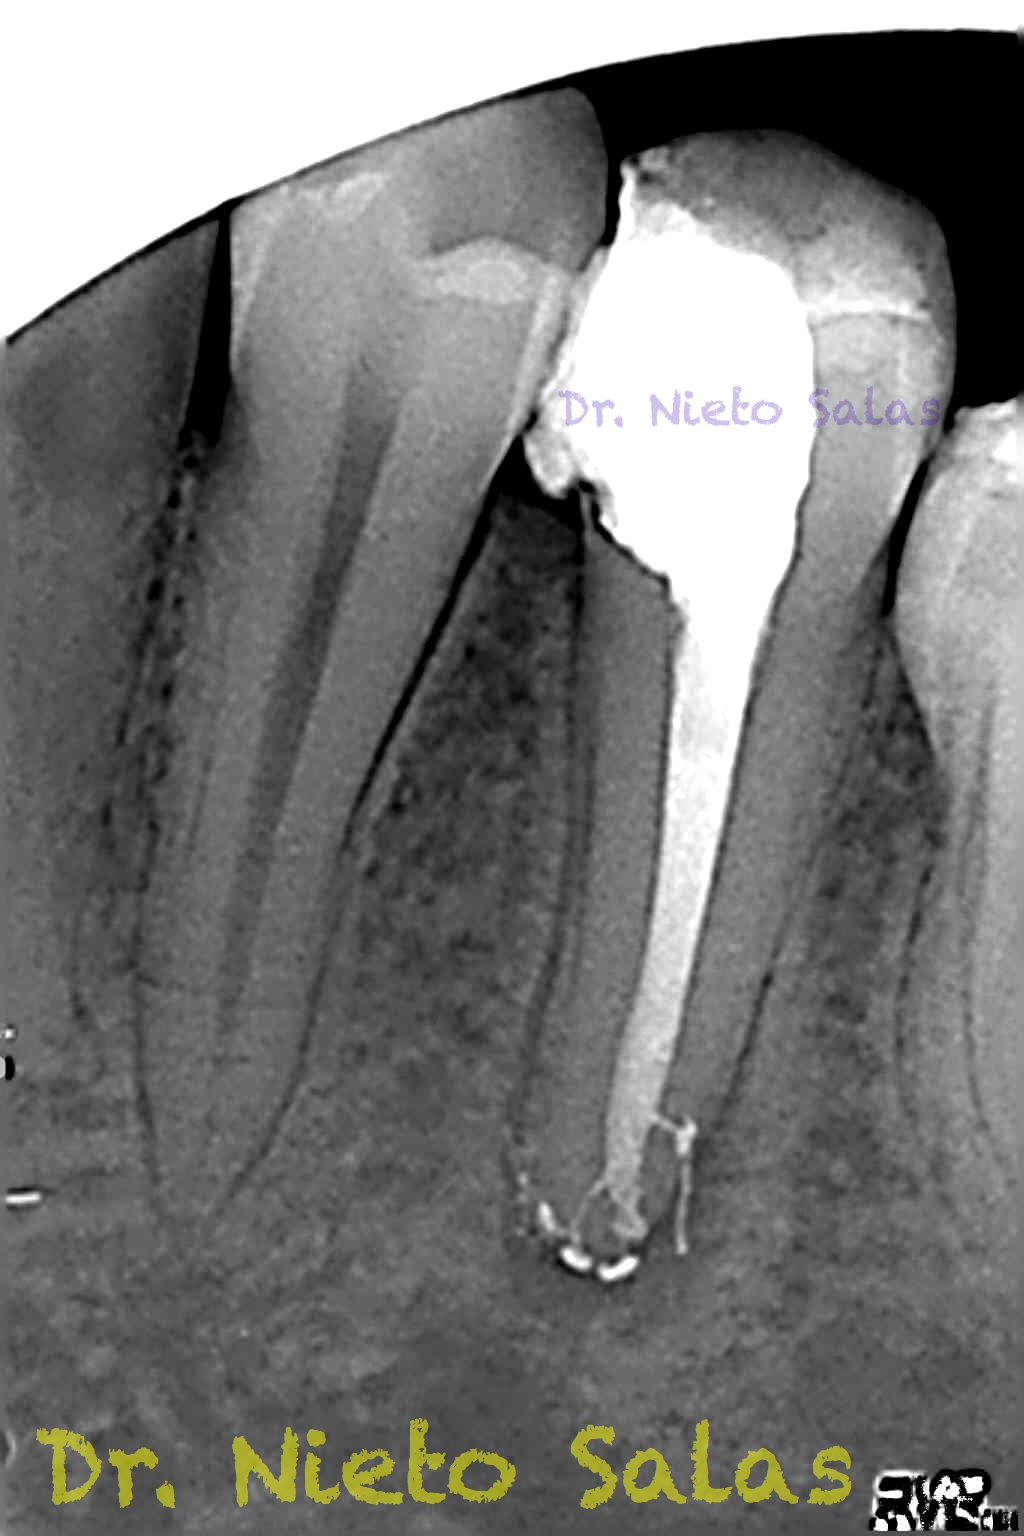

Nos llega a la clínica  este 4.5 con necrosis y periodontitis apical. la instrumentación se realizó con técnica de crown-down con limas K3 (SybronEndo) y la obturación con la técnica de ola continua de Buchanan, el tiempo de trabajo (para mi bastante importante) sobre 70-90 min.

Pero no todo se va a dejar al «poder de la irrigación»,  es muy importante la biomecánica, y la intuición para poder instrumentar esos pequeños conductos laterales que es muchas ocasiones nos dan problemas. Así, pues, os pongo un par de casos que con ayuda de esta «intuición» pudimos hacer un buen tratamiento.

Una vez que hemos desbridado biomecánicamente con limas de muy pequeño diámetro, obturamos: